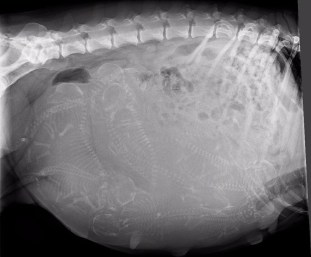

At 48-55 days of pregnancy, we do an X-ray to get an approximate head count on puppies. This is very important so that we are prepared for how many puppies we think we may be having and to know when we are done or close to done with whelping. Counting puppies via X-ray is an art and very rarely an exact science. Can you tell how many puppies are in this X-ray?

(answer: 10 puppies)